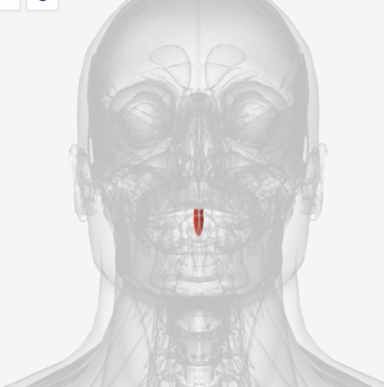

Musculus uvulae

origin is on the posterior nasal spine of the palatine bones, coursing the length of the soft palate to insert on the mucous membrane that covers that velum; function is to shorten the soft palate

Musculus Uvulae

|  |  |

Musculus uvulae

I